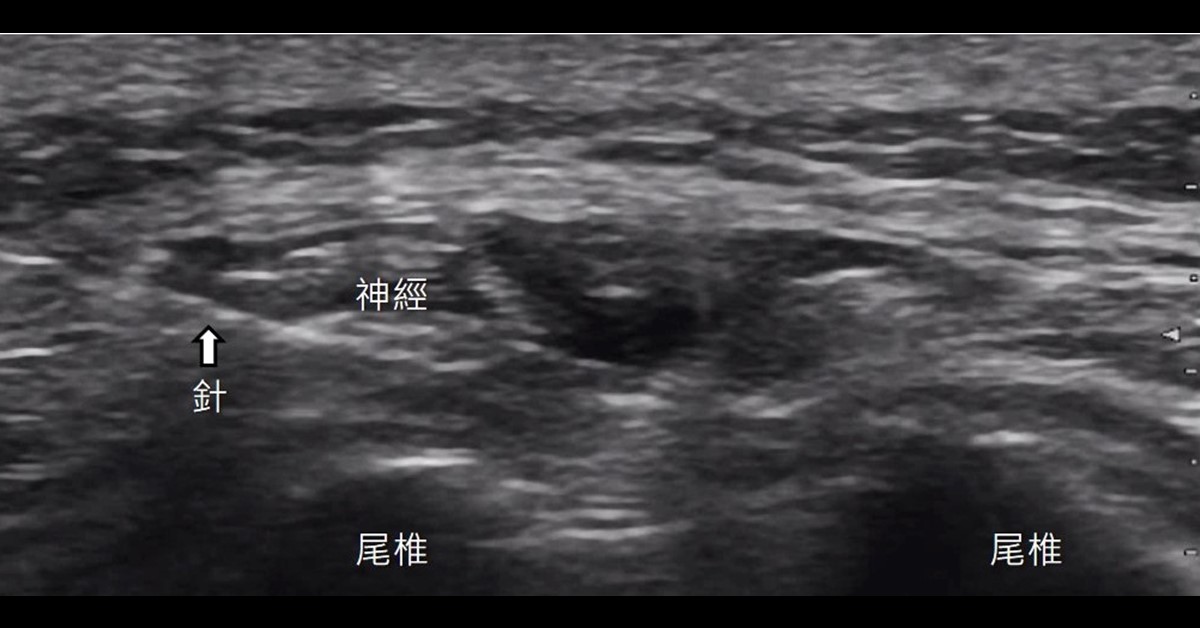

配合使用高解析度超音波,可以幫助醫師判別是否合併急性發炎或其他軟組織受損,並依病人的情況給予個別化治療。在急性期發炎期,可斟酌給與少量類固醇注射,並將堆積的組織液抽吸乾淨;在慢性期,則給予多次葡萄糖增生療法、高濃度血小板血漿或玻尿酸注射則較為適當。